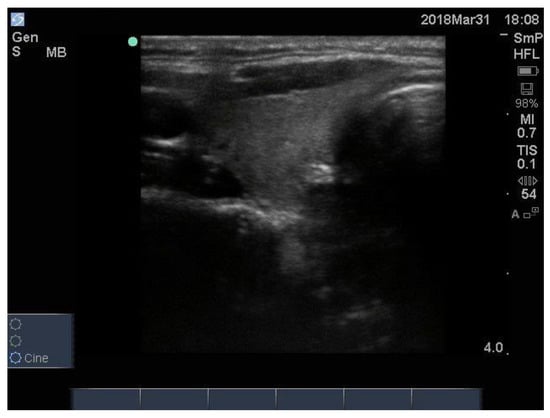

In Hashimoto thyroiditis the blood supply to the gland increases during the early inflammatory stages, but later, when the inflammation has burnt out and the gland is scarred and empty, the overall blood supply is markedly reduced. Examples of the two types of end stage disease are seen in Figure 16.

Figure 16.

Thyroid ultrasound findings in 2 patients with different features of late-stage Hashimoto thyroiditis. In (A) the dominant feature is diffuse hypo echoicity, seen as black “holes” indicating the absence of thyroid tissue, some scarring, decreased vascularity and architectural damage in an overall enlarged gland. In (B), the thyroid gland is now shrunken, scarred and shrivelled with pseudo nodules and scattered fibrous bands in a small gland; this is the final stage and the patient has no thyroid function.